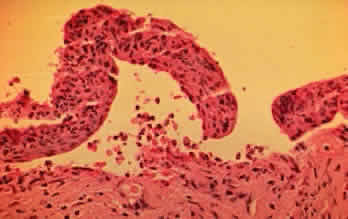

In the early stages of conjunctival disease, granulation tissue is found beneath the conjunctival epithelium, with an infiltration predominantly of lymphocytes and plasma cells, with occasional eosinophils and relatively few neutrophils.13,26 Later, pronounced fibrosis takes place in the conjunctival stroma and is responsible for the conjunctival shrinkage that characterizes the disease.9,10 Hyperproliferation of conjunctival fibroblasts from patients with CP has been demonstrated in tissue culture.29 One study described perivascular inflammatory cell infiltration in 20% of specimens and substantial mast cell participation and degranulation.4 In addition to the chronic inflammatory cells typical of CP, conjunctival biopsy specimens from patients with acute manifestations of CP show numerous neutrophils within and beneath the conjunctival epithelium (Fig. 8).15